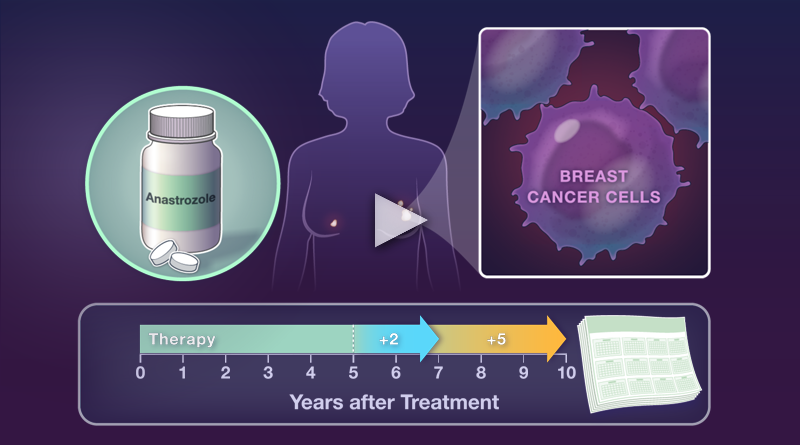

Running series of animated visual abstracts, Quick Takes, created for The New England Journal of Medicine as part of a team of illustrators, medical writers, and scientists. These short, iconographic animations aim to succinctly describe clinical trials and increase the awareness and understanding of important research findings.

Adopting The Journal’s visual style and asset library, I am responsible for the entire production process including narration editing, storyboarding, layout, illustration, and animation.